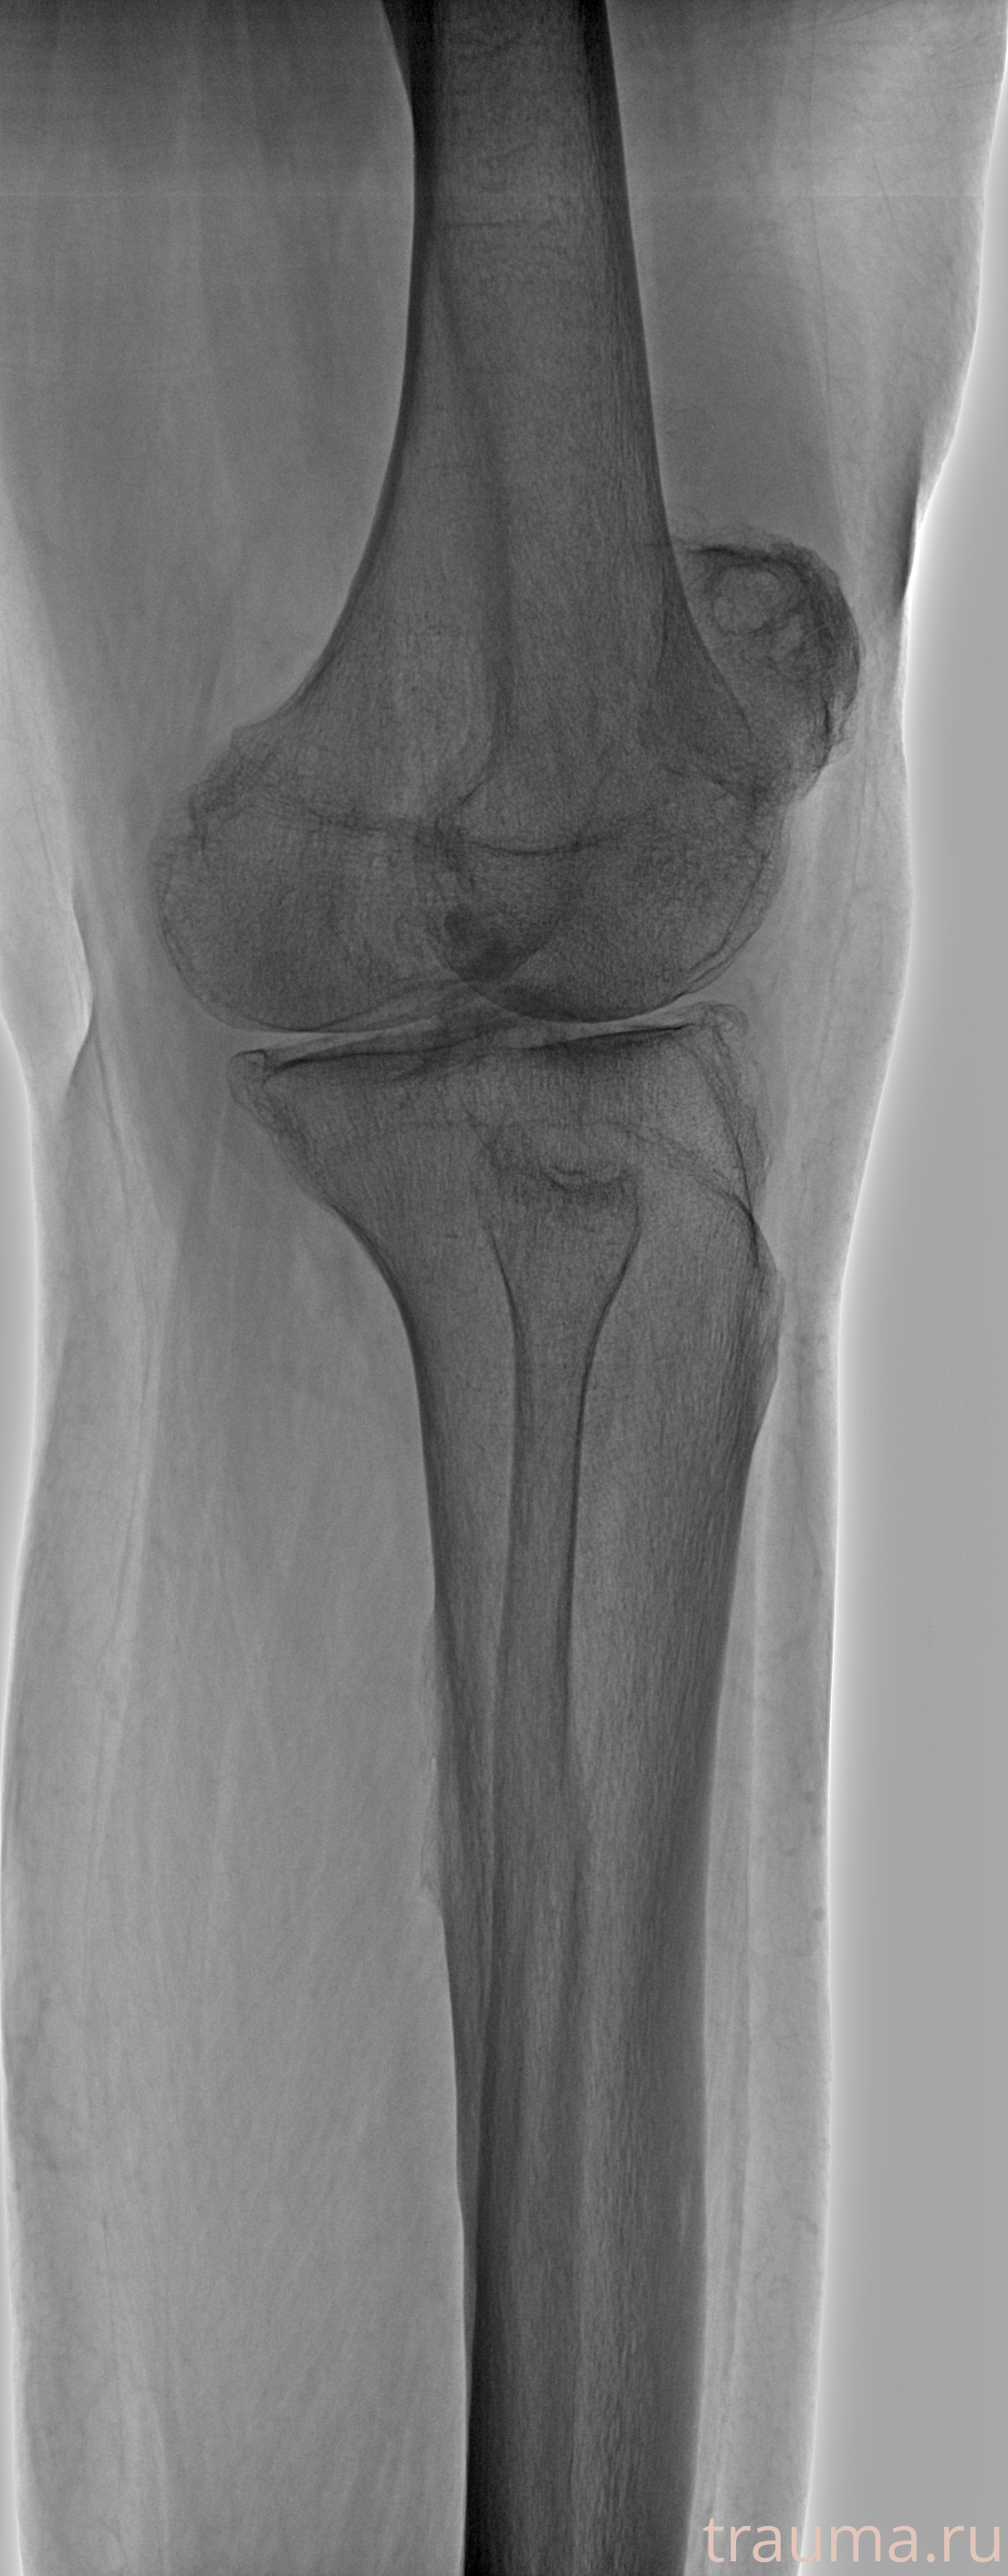

Рентгенограммы

Рентген на дому: по вашему адресу приезжает врач-рентгенолог, травматолог-ортопед с мобильным рентгеновским аппаратом, проводит диагностику травмы или заболевания, делает необходимые рентгенограммы, дает рекомендации по дальнейшему лечению. Получить качественные снимки в домашних условиях возможно благодаря уникальной методике, разработанной МосРентген Центром для института  Склифосовского